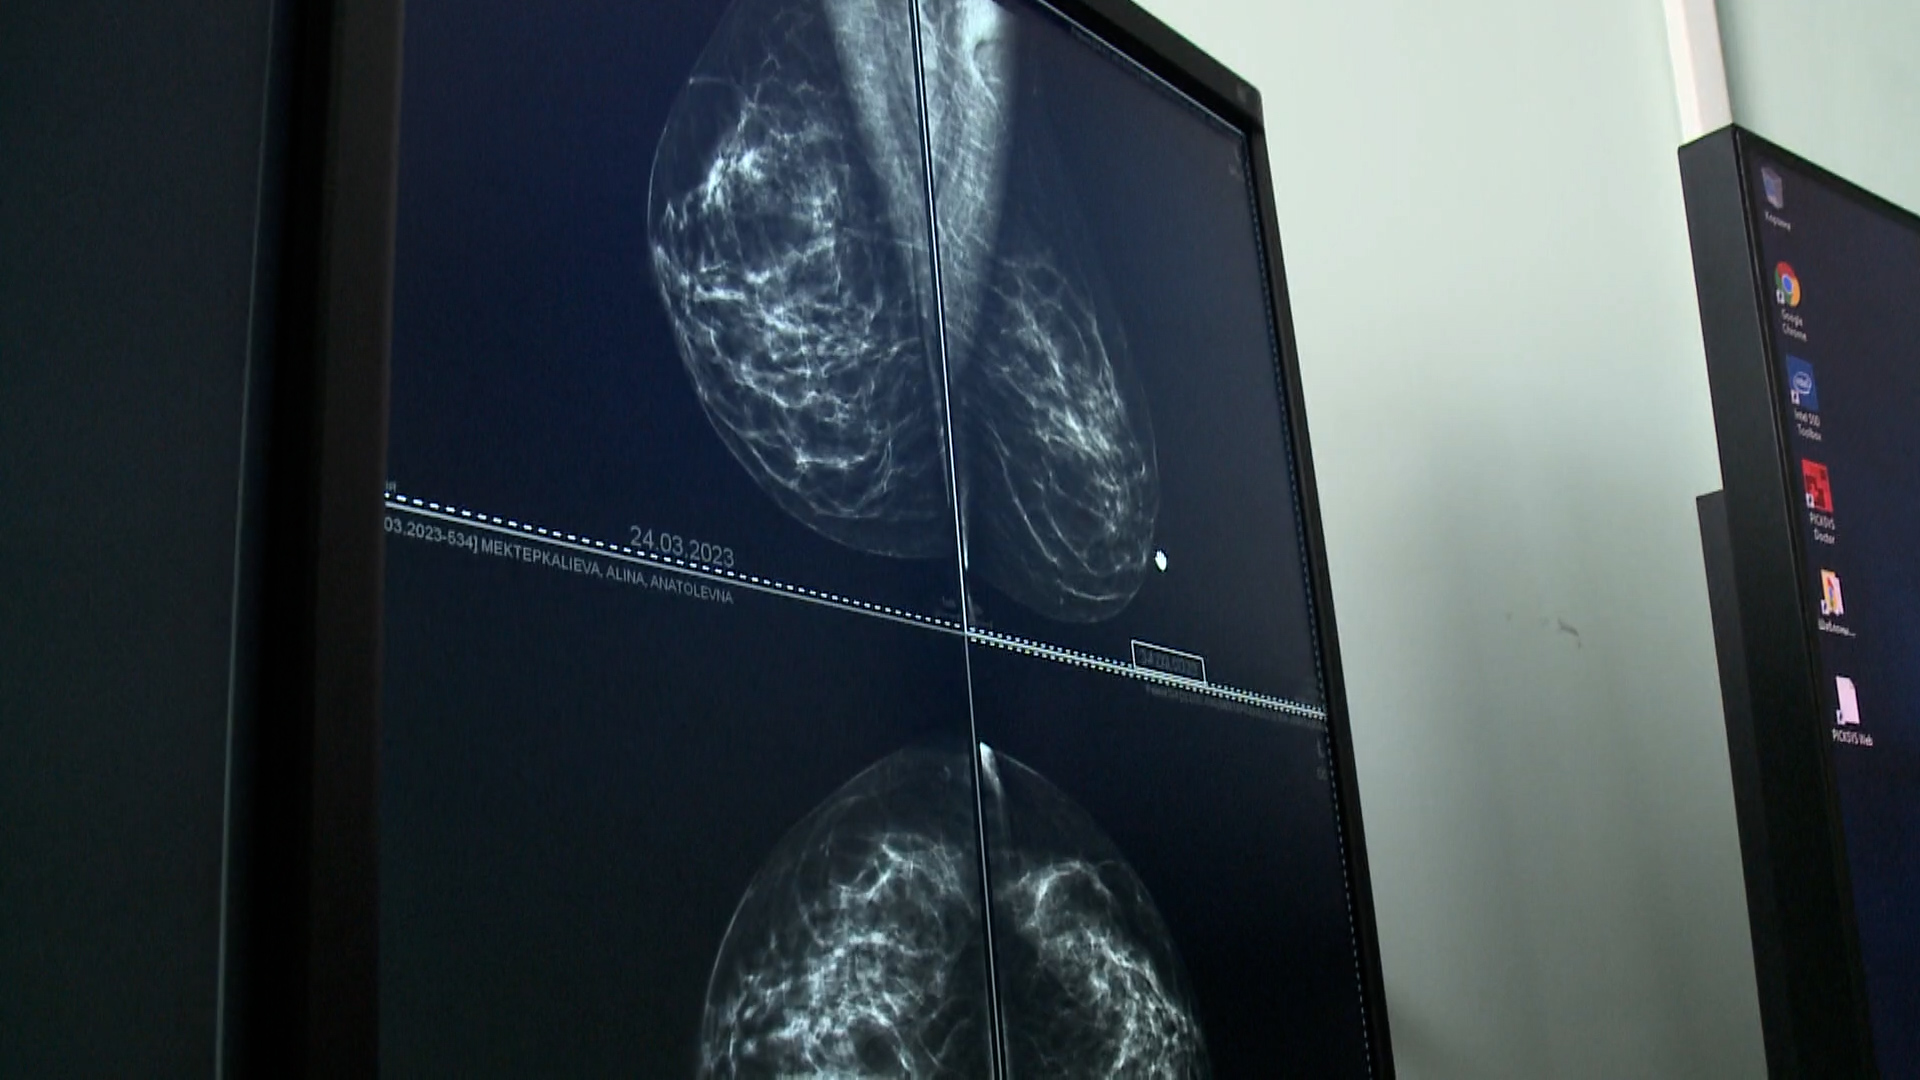

Пост принял. В таркосалинской центральной районной больнице заступил на службу новый доктор. В штате медучреждения теперь работает врач-онколог Роберт Мирсояпов. На новом месте работы его встретили радушные коллеги, доктор даже успел посетить отдаленные поселения.

На новом месте Роберт работает почти 2 месяца, но уже смог принять пациентов в Ханымее и Харампуре. С появлением второго онколога больница чаще может проводить профилактические работы с населением, отправлять врачей в отдаленные поселения.

Выездные обследования организуют регулярно. Пациентов принимают кардиолог, эндокринолог, невролог и другие врачи узкой специализации. С января мобильная бригада врачей выезжала в отдаленные поселения около 80 раз – это более 1000 осмотров и консультаций пациентов.